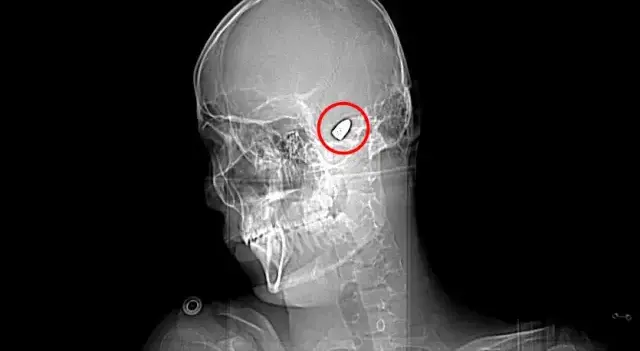

Batman'ın Bahçelievler Mahallesi'nde, 5 Kasım 2023 tarihinde yaşanan o 'korkunç' olay, genç Yusuf Emre Özbek'in hayatını 'kökünden' değiştirdi. Arkadaşları ve ağabeyiyle maça gitmek için evden çıkan Yusuf, topluca fotoğraf çektirdikten saniyeler sonra aniden yere yığıldı! Hastanede çekilen röntgen filmi ise 'dehşet verici' gerçeği ortaya çıkardı: Yusuf'un kafasında bir mermi çekirdeği vardı! 4 gün yoğun bakım ve 4 gün de serviste süren tedavi sürecinin ardından doktorlar, merminin 'hayat damarlarına' yakın, riskli bir bölgede olduğunu belirterek müdahale etmenin 'imkansız' olduğunu açıkladılar.

O andan itibaren Yusuf için 'kabus dolu' bir süreç başladı. Konuşma güçlüğü, yürüme zorluğu ve sağ elindeki 'gizemli' zayıflık... 1.5 yıl boyunca süren yoğun fizik tedavi seansları, Yusuf'u yeniden hayata bağlasa da sağ elini kullanmakta ve parmaklarını oynatmakta hala büyük zorluk çekiyor. Ancak fiziksel sorunların ötesinde, Yusuf'un asıl mücadelesi kafasındaki o 'sessiz katil'le! "Kafamda bir mermi ile yaşadığım için ölüm korkusu yaşıyorum. Sürekli bir tedirginlik içerisindeyim" sözleriyle yaşadığı 'psikolojik bombardımanı' dile getiriyor.